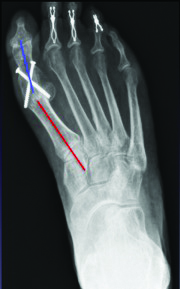

While the technique and use of bone transport can provide success while keeping the first ray out to an appropriate length, one must be mindful of the soft tissue envelope and the lack of intrinsic musculature when performing this procedure. It is also important to base the vector of transport to the distal pins and lengthen parallel to the ground to avoid metatarsus primus equinus. We recommend preserving the metatarsal parabola (approximately 142 degrees with the first metatarsal equal to the third metatarsal). Consider bone transport procedures in two stages on the first metatarsal due to the likely requirement to fuse the distal regenerate bone with the base of the proximal phalanx. In keeping with principles of bone transport and tibialization of the fibula, one can also perform gradual transverse medialization of the second metatarsal and docking with the medial cuneiform and proximal phalanx successfully. Authors have described fibular bone hypertrophy occurring over the course of five years and it is therefore plausible for the second metatarsal to hypertrophy as well.44,45